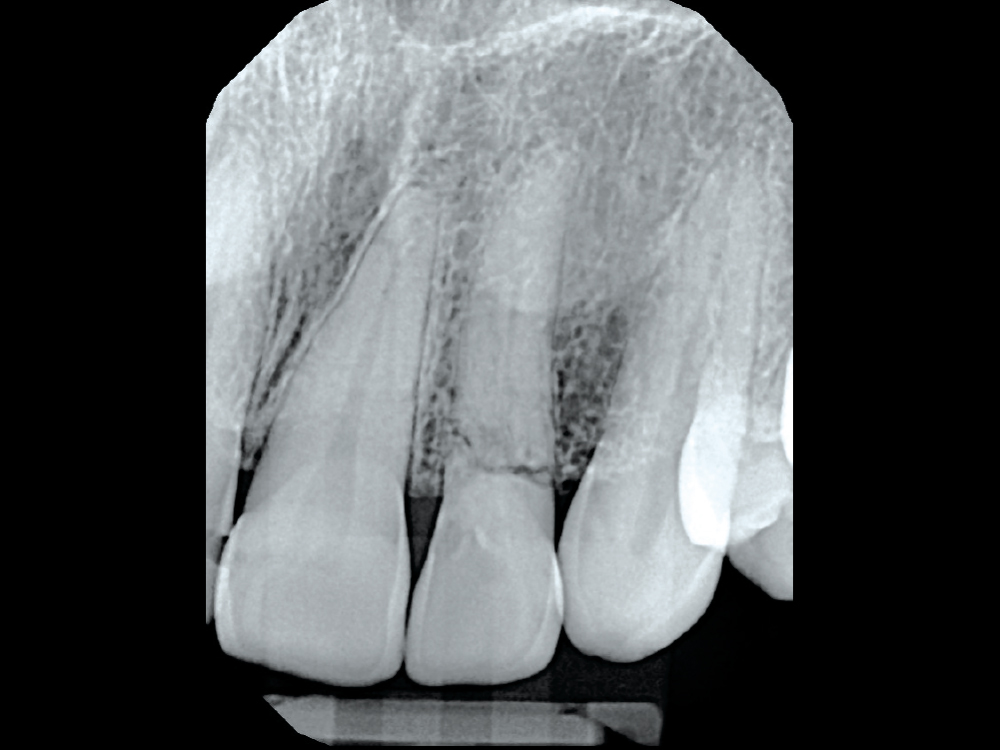

The radiograph shows what we cannot see clinically.

Figure 2: The radiograph shows what we cannot see clinically. The trauma the patient described most likely caused the horizontal fracture to tooth #10. As a result, over time the tooth became ankylosed. Treatment options were discussed with the patient and ultimately the patient elected to have the tooth removed and an implant placed.